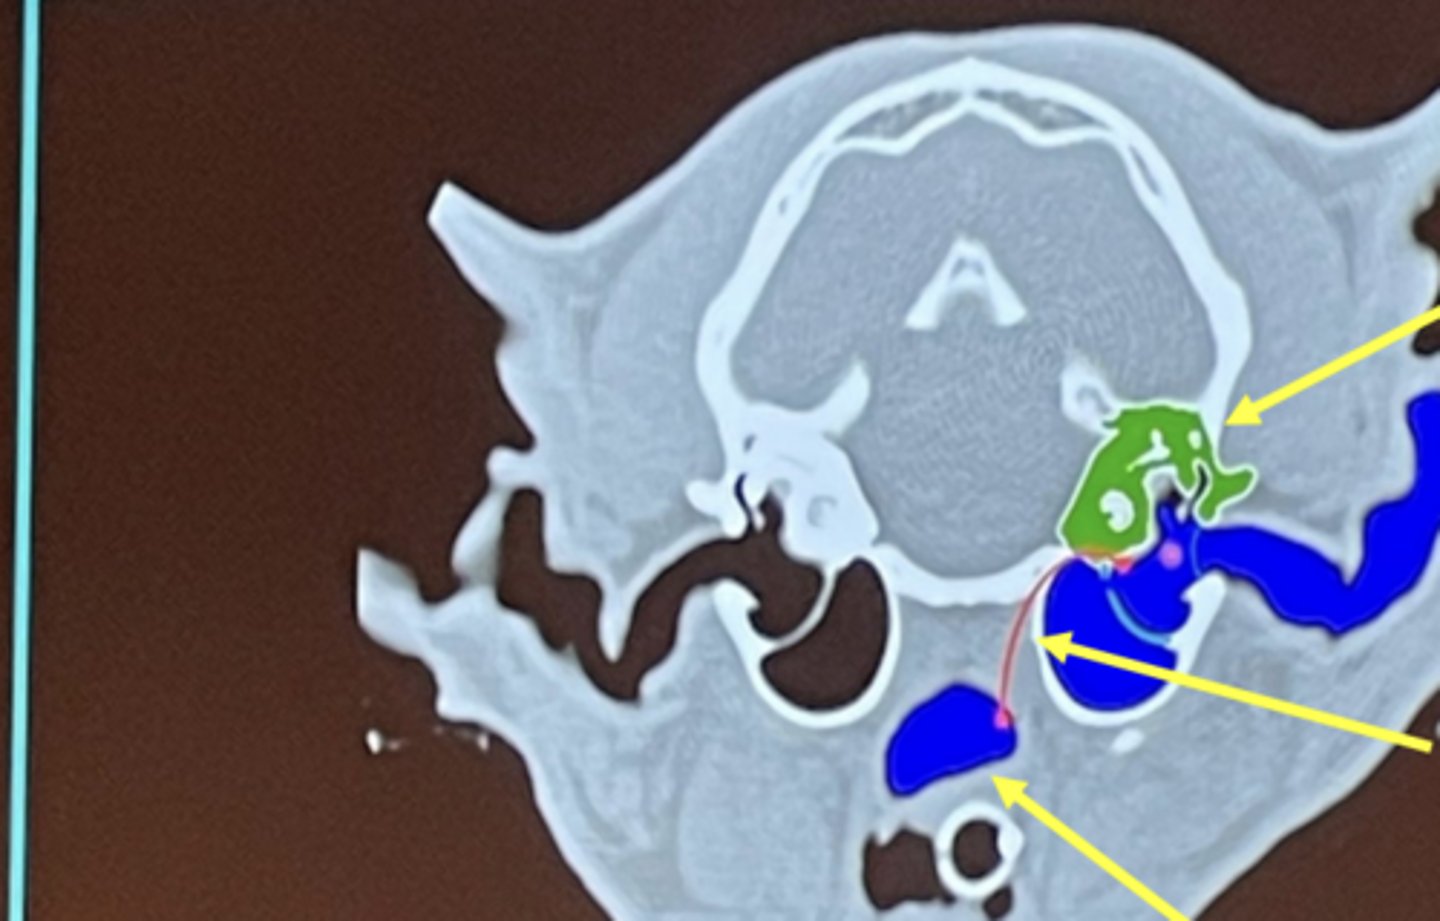

What are the top differential diagnoses for this image?

1. polyp

2. infection (otitis media)

What is being highlighted in yellow?

external ear

What is circled?

middle ear

What is the top arrow pointing to (green)?

inner ear

What is the middle arrow pointing to?

eustachian tube

What is the bottom arrow pointing to?

nasopharynx